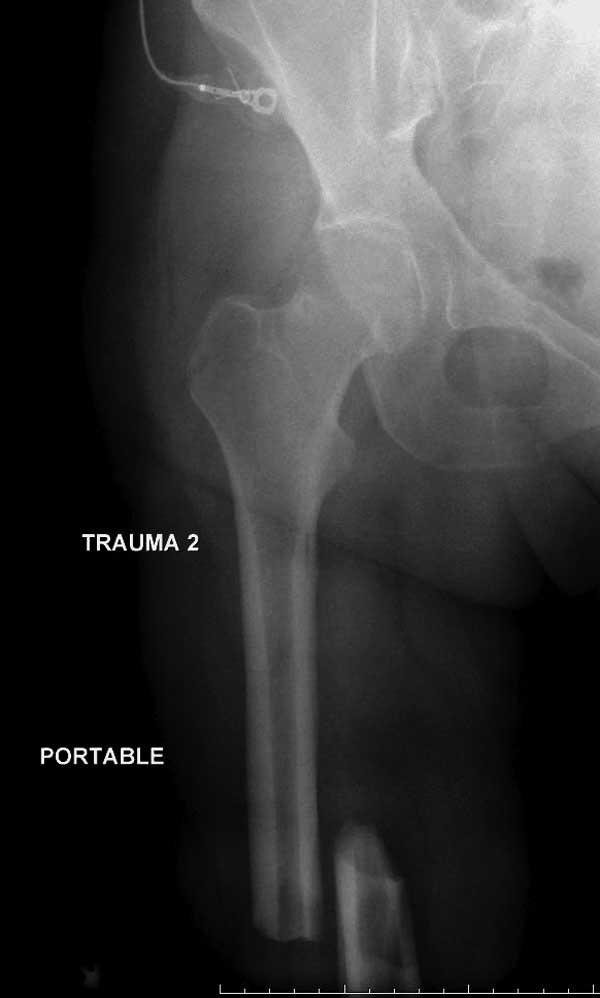

Женщина 28 лет, политравма.

По протоколу обследования больных с травмой сделаны все исследования и выставлен диагноз: разрыв печени и селезенки; множественные переломы ребер и лицевого черепа; стабильный перелом позвоночника, переломо-вывих головки левого бедра, перелом диафиза правого бедра, переломо-вывих правого тарана.

Имя     : 1 Fem diaphys fem neck 1.JPG

Тип     : image/jpg